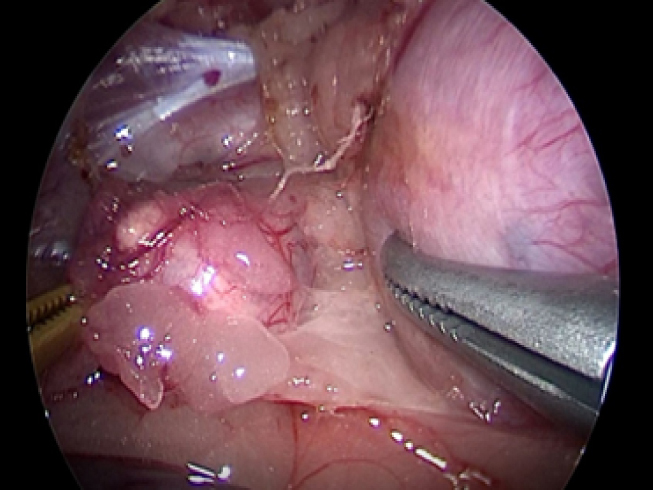

腎臓と副腎の間を剥離していきます。 ここでも腫瘍の周りには豊富に血管があるので丁寧に剥離していきます。

実際の手術風景です。